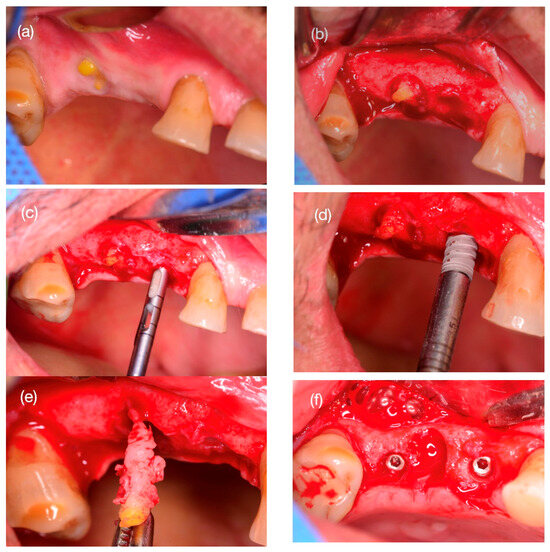

2.5. Step 2: Bone Biopsy Surgery and Implant Installation